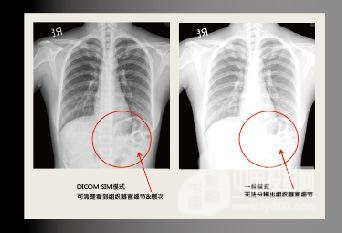

支持DICOM.SIM醫(yī)療設(shè)備模擬顯示模式

DICOM.SIM 顯示模式能夠使投影機(jī)模擬醫(yī)療設(shè)備的灰度/Gumma性能來顯示圖像,相對(duì)沒有沒有DICOM模式的投影機(jī),可以更精準(zhǔn)地表現(xiàn)灰階圖像,且清楚地傳達(dá)醫(yī)療訊息,有助于診斷&治療細(xì)節(jié)討論。 注:此模式僅用于教育培訓(xùn)或會(huì)議討論,醫(yī)療診斷禁止使用!